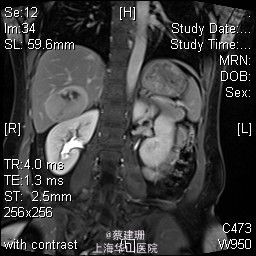

主诉:平滑肌肉瘤、肝转移癌术后,发现肝多发转移2月余。 现病史:患者3年前外院检查发现后腹膜肿瘤,外院行后腹膜肿瘤切除术后,术后病理为:平滑肌肉瘤,2013年12发现肝左叶转移癌,外院行肝左叶肿瘤切除术,术后病理为:梭行平滑肌肉瘤。2月余前患者复查发现肝脏多发转移,2015-4月肝脏MRI:肝脏多发转移。现患者无恶心、呕吐,无呕血、黑便,无皮肤巩膜黄染,无剧烈腹痛发作。现为进一步诊治收住入院。

查体:锁骨上淋巴结未扪及肿大;腹部平坦,可见陈旧性手术疤痕。未见肠型、胃型蠕动波,腹软,无压痛及反跳痛,无肌卫,肝脾肋下未及。Murphy’s 征(-),肝区叩击痛(-),肾区叩击痛(-);移动性浊音阴性。 辅查:2015-4月肝脏MRI:肝脏多发转移。

诊断 :1、多发肝转移癌 2、后腹膜平滑肌肉瘤术后 3、肝转移癌术后 处理:取右侧肋缘下切口,左侧延长,逐层切开进腹,探查腹腔:见上腹部粘连,仔细游离上腹部腹腔粘连,探查见无腹水,胃、肠、胰、脾及盆腔脏器未及异常,腹腔未见明显转移结节;肝脏无硬化。肝门淋巴结无肿大,门静脉主干无栓子。肿瘤多枚,最大两枚位于肝右叶VI段,肿瘤大小约7*6*5cm。V段肿瘤直径约5cm。左内叶肿瘤多枚,直径0.5-4cm,紧贴第一肝门。左外叶肿瘤多枚,直径1-3cm,肿块质韧,边界尚清,有包膜。术中诊断为转移性肝癌,决定行左半肝切除,肝右叶特殊肝段切除。